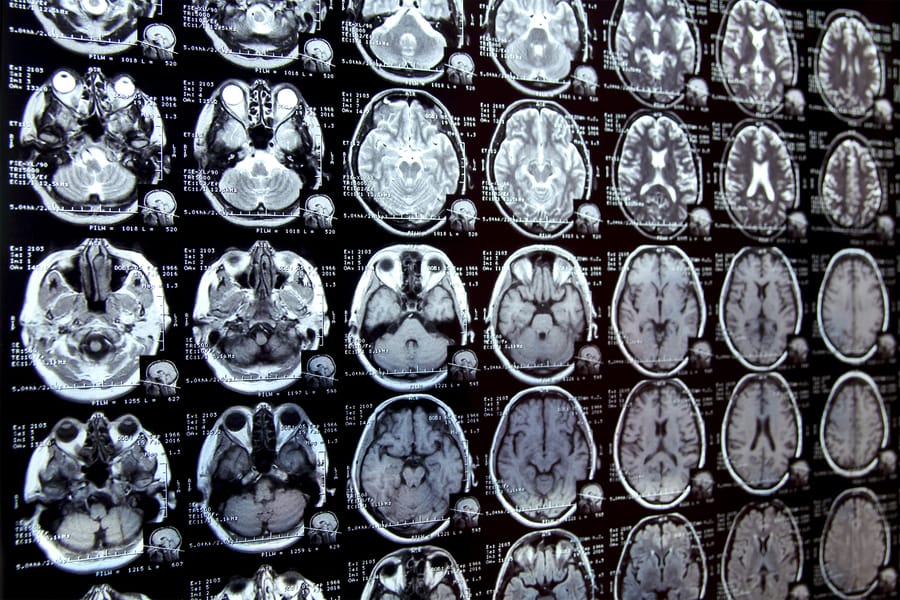

🤖MIT Develops New AI Tool to Accelerate Medical Image Segmentation with a Click

The Innovation: Segmenting medical images—painstakingly outlining tumors or organs—is a massive bottleneck in diagnostics and research. MIT researchers have developed a new AI tool where an expert can simply click on or roughly doodle over a region of interest, and the model instantly and precisely segments the entire structure. The tool uses a "foundation model" pre-trained on millions of non-medical images, allowing it to understand objects with incredible speed and minimal human input.

The Real-World Impact: This could save clinicians and researchers countless hours, accelerating everything from surgical planning to the pace of clinical trials. By making expert-level segmentation accessible with a click, it democratizes a critical medical imaging task and allows experts to focus on analysis and diagnosis, not tedious outlining.